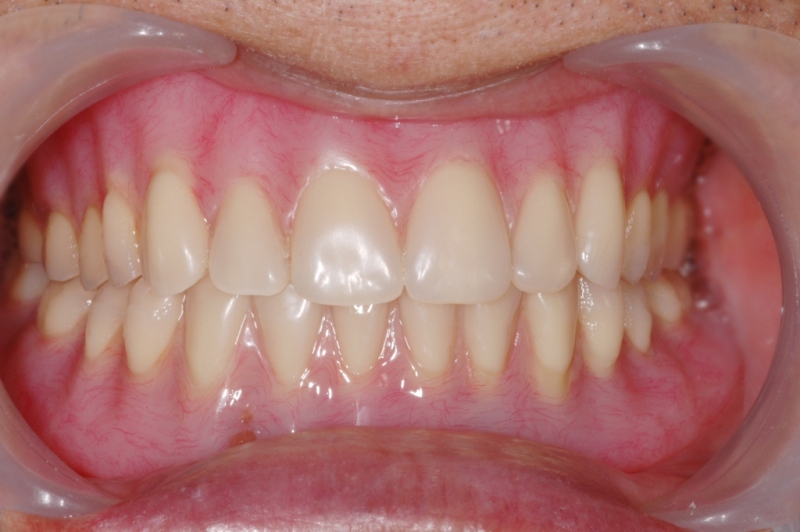

案例1